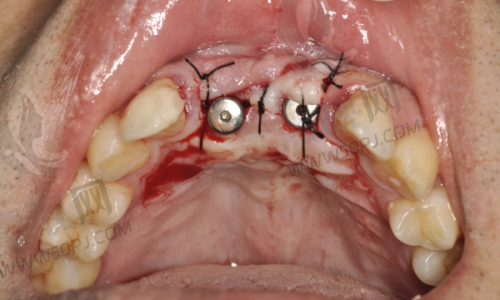

前身格莱美就已经在种植牙领域小有成绩,而今以“米兰柏羽”的新身份回归,诊疗项目更细化,技术和设备全线升级,比如高精度的椅旁CEREC系统、3D数字化导板种植系统等精良设备,统统上线。

原来的“基础版”,现在直接升级“豪华版”:别墅级就诊环境+数字化精细诊疗+原装进口种植体,这波升级,确实不水。